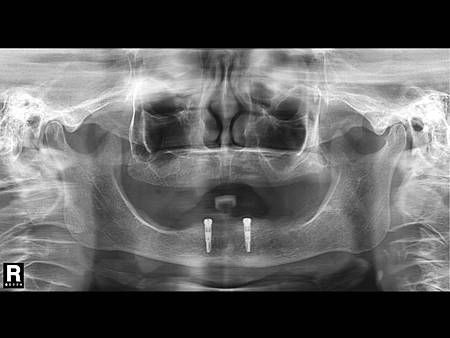

患者術前x光片

經評估後植入兩顆xive德國製人工植牙增加下顎支撐

完成圖, 如此一來下顎假牙因下方有植牙支撐, 改善咬合功能 , 以現在的全口假牙標準, 一般建議下顎至少要有植牙2~4顆, 植牙越多的話患者咬合功能可以恢復得更多